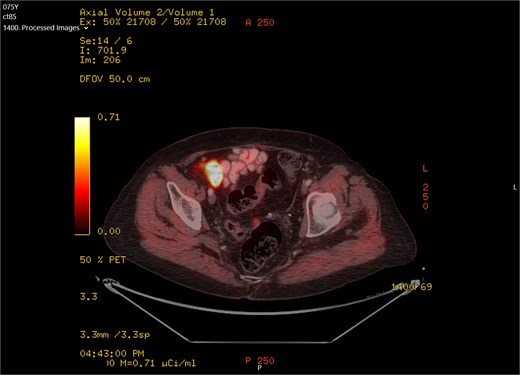

A 75-year-old woman with a past surgical history of serous papillary ovarian carcinoma underwent complete debulking surgery and adjuvant chemotherapy treatment 2 years prior to her current presentation. During follow-up, increased FDG uptake along with a 1.2-cm mass was seen on a PET-CT on the serosal surface of the recto-sigmoid junction (Fig. 1). An attempt was made to evaluate the lesion using trans-rectal sonography. Radial sonographic view showed a 12 mm, hypoechoic, well-defined lesion located at the serosal surface of the recto-sigmoid junction (Fig. 2). After reverting to a linear view, the lesion was sampled with fine-needle biopsy (Fig. 3) and whitish thick cores were retrieved (Fig. 4). The procedure was uneventful and no adverse events were noted. Pathology revealed fragments of high grade serous carcinoma of tubo-ovarian origin. Relying on the histological information gained from the biopsy, it was known that the lesion although not obvious to the eye during surgery, had to be found and resected. The surgical procedure was challenging with multiple adhesions, which made it difficult to locate the lesion. Based on the valuable preoperative knowledge, the patient was able to have a complete debulking of the tumor mass.

Radial sonographic view of the malignant lesion at the 2 o'clock position.